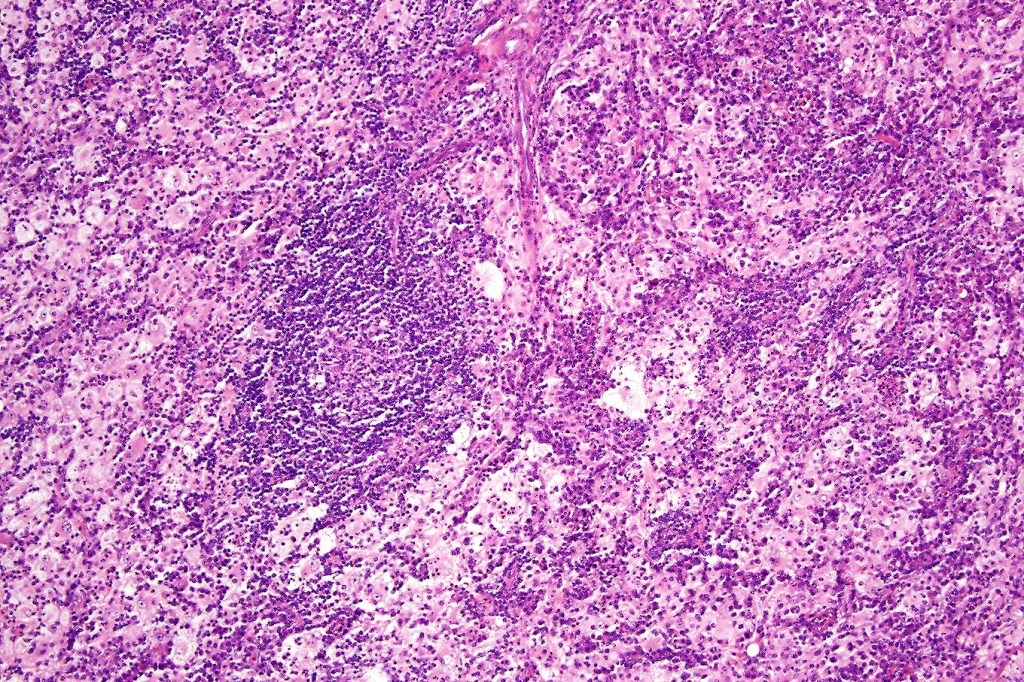

•Due to the admixture of pale histiocytes and lymphocytes, the scanning view is characteristic, and the diagnosis can be strongly suspected at this magnification

•Dense dermal nodular infiltrate sometimes extending into subcutaneous fat

•Emperipolesis of lymphocytes, plasma cells & neutrophils

•Background population of lymphocytes, plasma cells, neutrophils, eosinophils & variable numbers of xanthoma cells

•Lymphoid follicles with germinal centers sometimes present